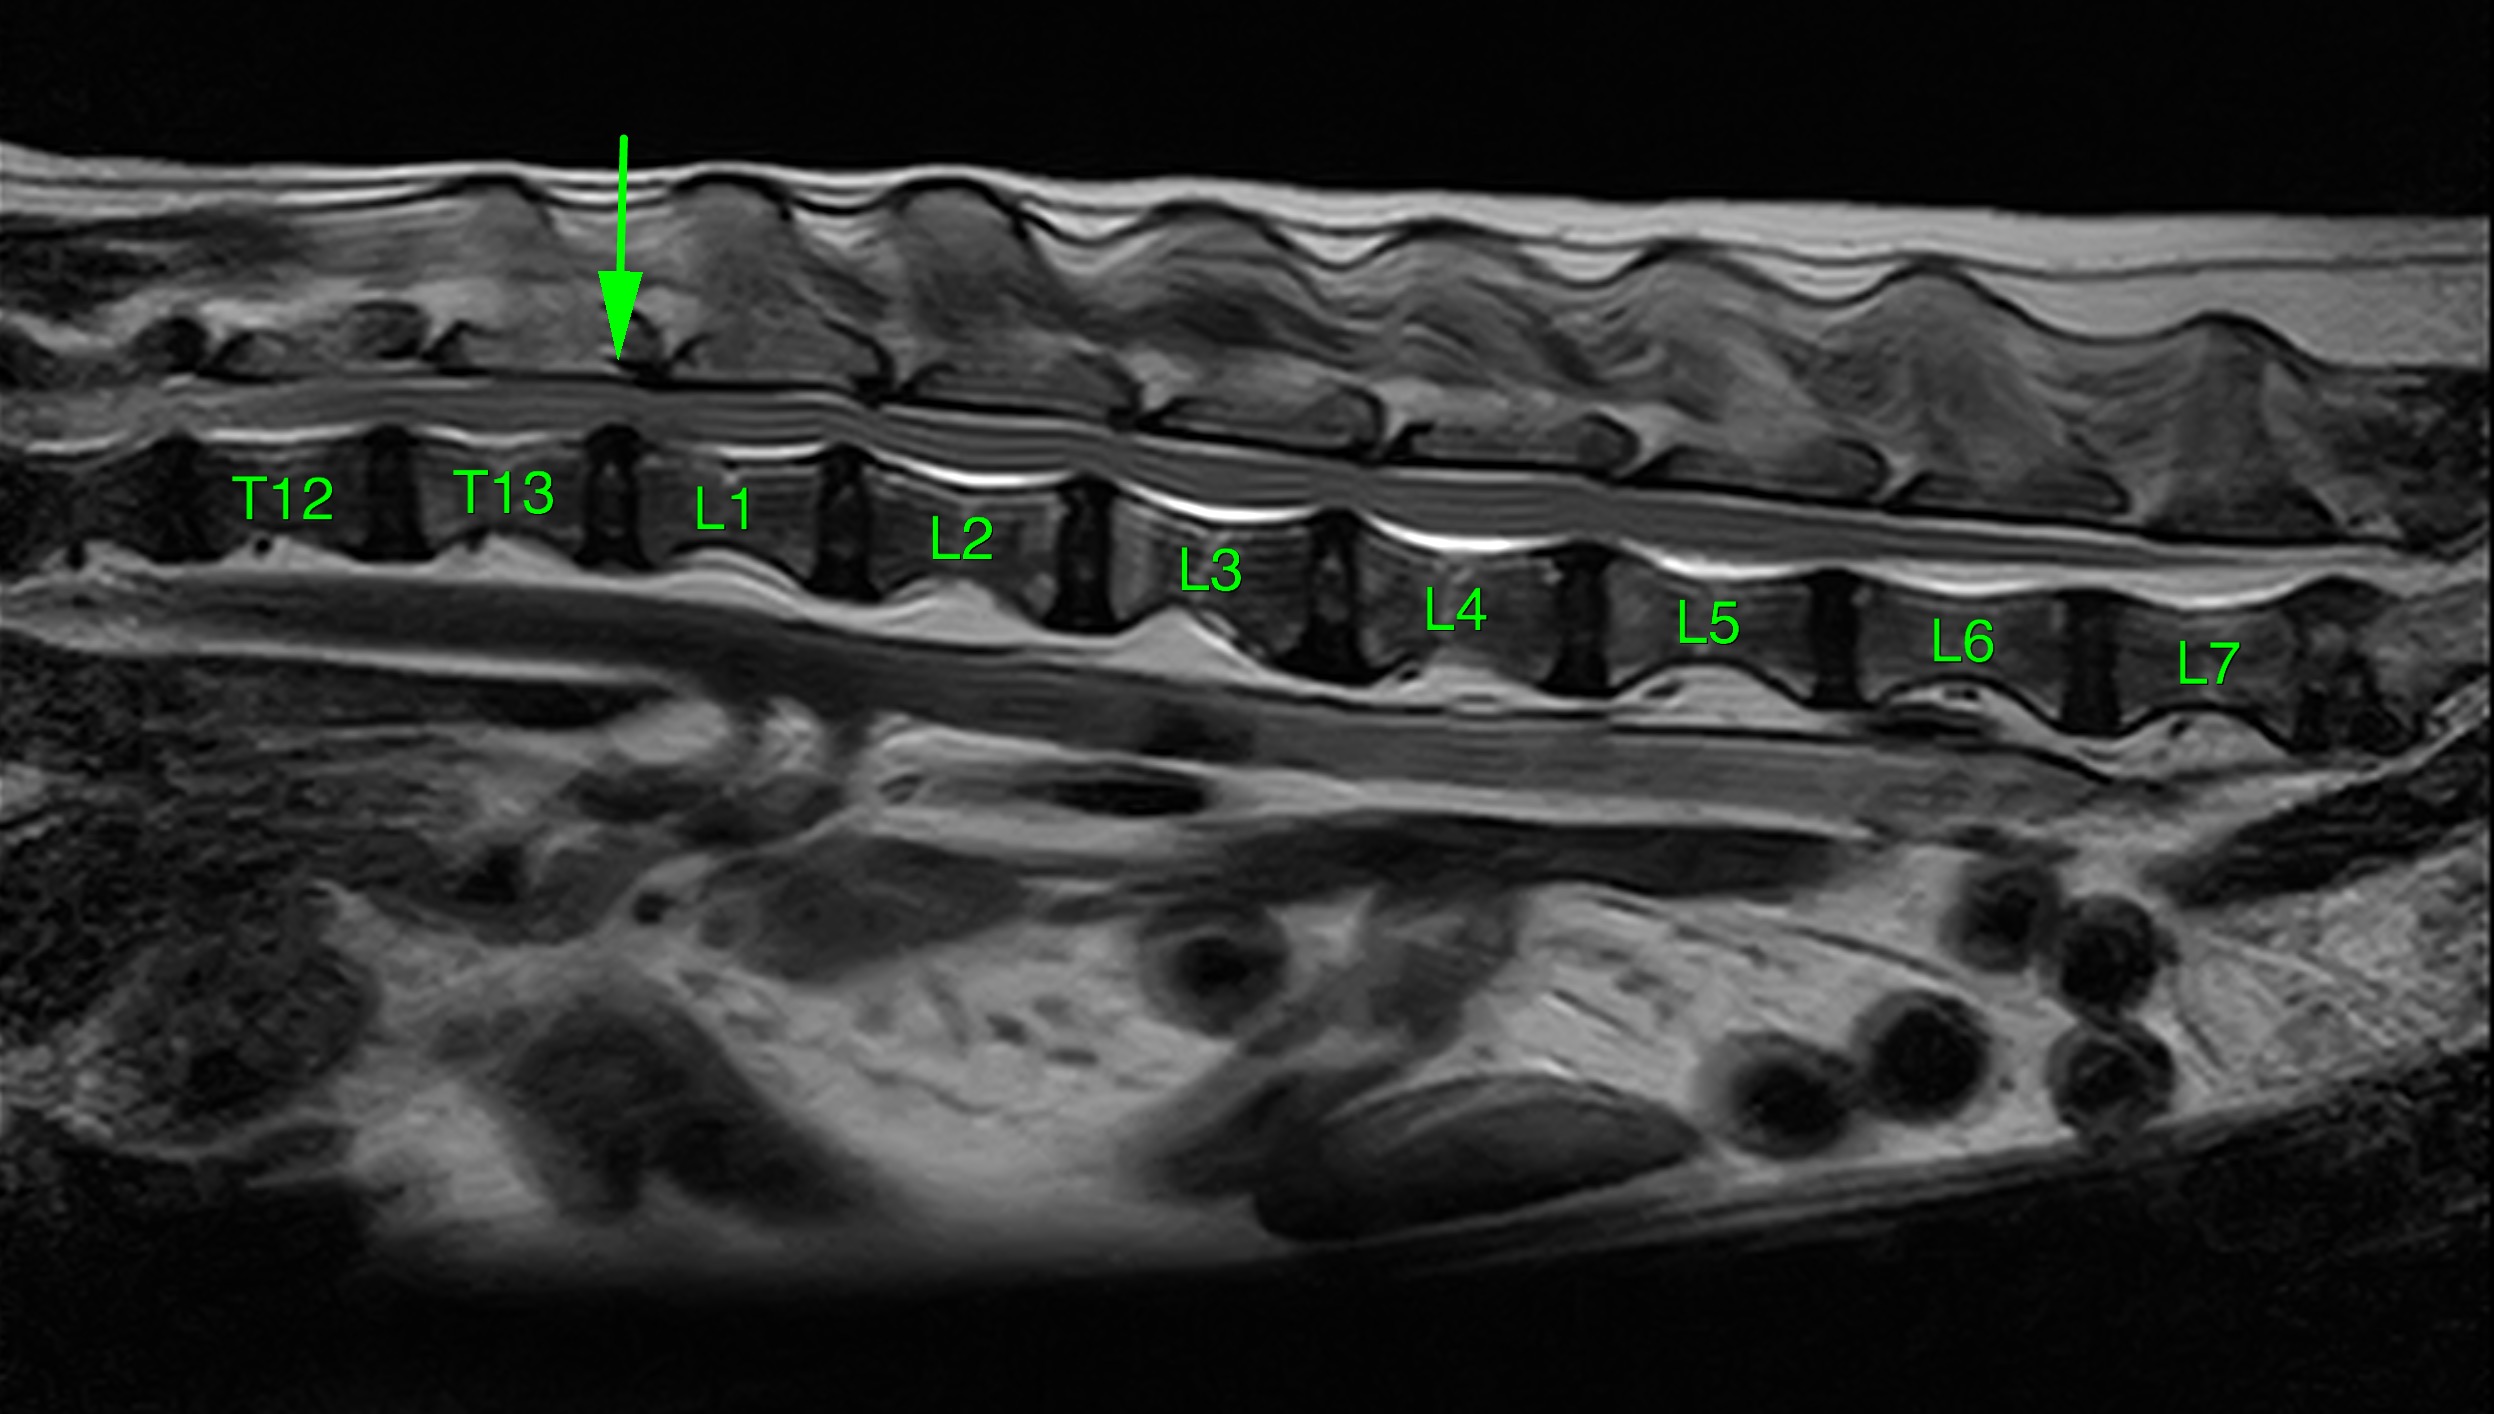

MRI画像(T2-Sagtal像:T13-L1間にて圧迫所見を確認)

MRI画像検査の症例は右側片側椎弓切除術を実施しました。